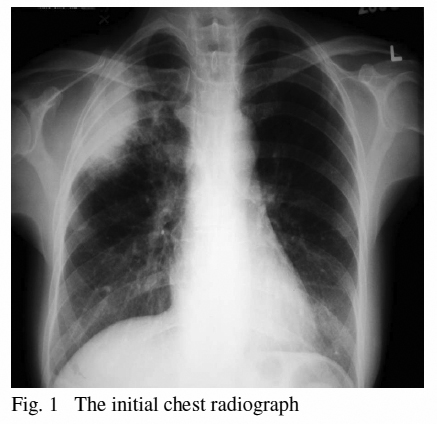

She was a non-smoker; non-drinker and enjoyed her good functional status. Her symptoms were only associated mild weight loss and reduced appetite. In reviewing her symptoms, she denied any dyspnoea, epistaxis, fever or nasal congestion. There was no relevant travel or contact history. On examination she was afebrile and all vital signs were stable. Inspiratory crepitations were noted over her right upper lung field. Initial chest roentgenogram revealed peripherally located right upper lobe infiltrate. (Fig. 1)